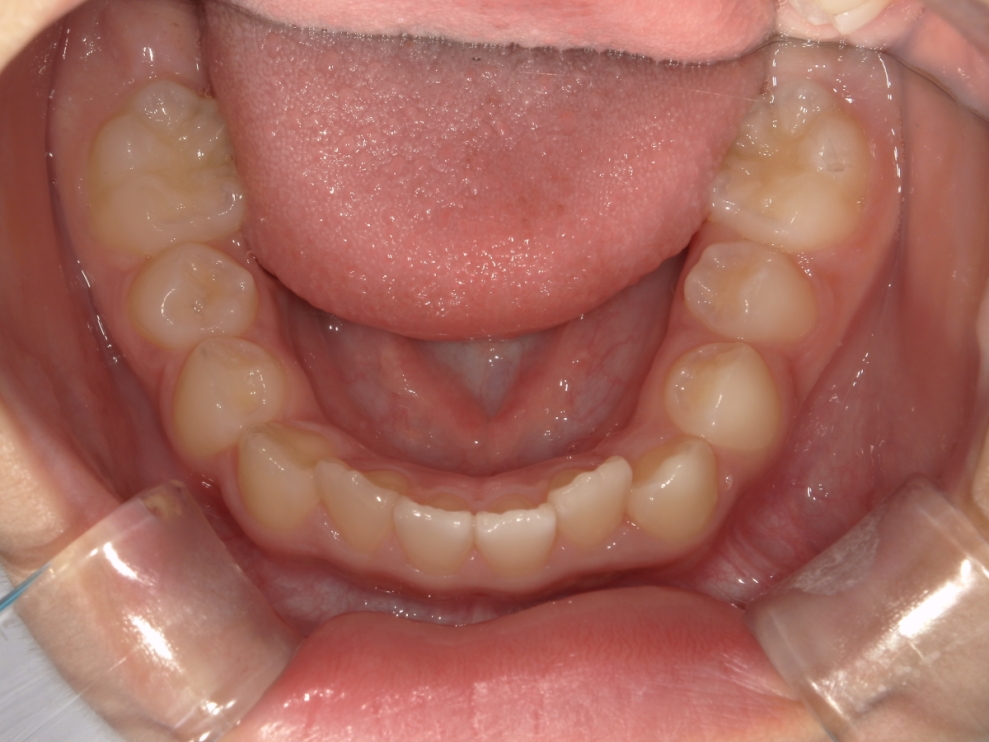

BEFORE

スタート時9歳の患者さまで、主訴は上下前歯のガタつきでした。早期に歯並びを整えたいとの思いからご相談に来院されました。

成長期であることを踏まえ、段階的な治療計画を立てました。まずプレオルソを1年1ヶ月使用し、口腔周囲筋や歯列のバランスを整えたうえで、その後、マウスピース矯正インビザライン・ファーストにて矯正治療を行い、さらに1年8ヶ月かけて歯並びを整えています。

治療期間は合計2年9ヶ月で、上下前歯のガタつきは改善し、見た目と機能の両面が整った歯列へと改善しました。